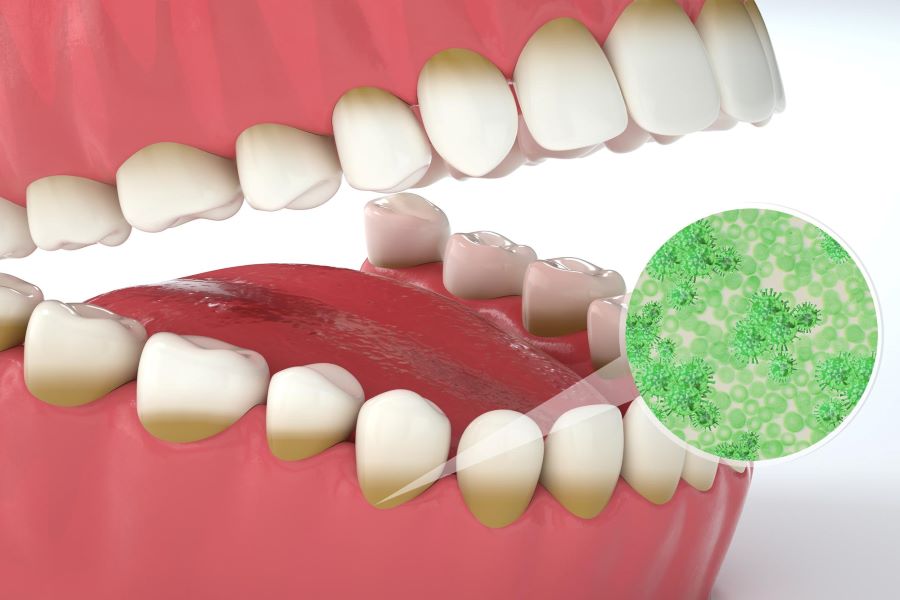

استفاده از دهانشویه

یک راهکار دیگر که میتوان برای سریعتر جوش خوردن ایمپلنت از آن یاد کرد، استفاده از دهانشویه است. دهانشویهها محصولاتی هستند که میتوان به کمک آنها میزان باکتریهای موجود در داخل دهان را تا حد قابل قبولی کاهش داد. افزایش شدید میزان باکتریها در دهان ممکن است منجر به بروز اختلالاتی در اتصال بین ایمپلنت و فک شود؛ به همین دلیل همه دندانپزشکان توصیه میکنند که پس از کاشت ایمپلنت از دهانشویه برای حفظ بهداشت دهان استفاده شود، البته بهتر است به سراغ دهانشویههای فاقد الکل بروید.

دکتر محمد عاطفت در رابطه با استفاده از دهان شویه در قسمتی از سایتش گفته است:

یکی از نکاتی که بعد از کاشت ایمپلنت باید حتما به آن توجه کنید تمیز نگه داشتن دهان است. استفاده از دهانشویه و شستشوی آنتی بیوتیکی و نمکی، محل کاشت ایمپلنت را ضد عفونی میکند. توصیه میشود دو بار در روز دهان خود را به مدت ۳۰ ثانیه با محلول شستشوی خوراکی Peridex شستشو دهید. از این محلول نیازی نیست به مدت طولانی استفاده کنید و استفاده دو هفته از آن کافی است. ۳۰ دقیقه بعد از استفاده از این محلول سعی کنید چیزی نخورید و ننوشید.

همه باکتریها و باقیماندههای مواد غذایی در دهان شما با مسواک زدن و دهانشویه به طور کامل از بین نمیروند؛ به همین منظور باید استفاده کردن از نخ دندان را به عنوان یک گزینه مهم در نظر داشته باشید. نخ دندان به شما اجازه میدهد تا کلیه مواد غذایی موجود در لابهلای ایمپلنتها و دندانهای خود را خارج کنید.

توصیه اصلی آن است که نخ دندان حداقل دو بار در روز مورد استفاده قرار بگیرد، البته شما میتوانید پس از مصرف هر ماده غذایی نیز از نخ دندان برای پاک کردن باقی ماندههای غذا در بین دندانهای خود بهره ببرید تا با حفظ پاکیزگی دهان، روند جوش خوردن ایمپلنت تسریع شود.